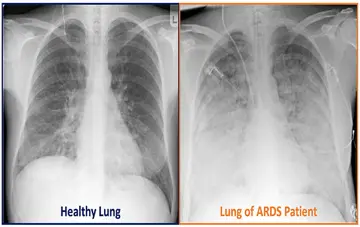

علائم ، عوارض و درمان سندرم دیسترس حاد تنفسی

بسیاری از افرادی که به سندرم‌دیسترس‌حاد تنفسی (ARDS) مبتلا می‌شوند جان سالم به در نمی‌برند. خطر مرگ با افزایش سن و شدت بیماری افزایش می‌یابد. اما افرادی که از سندرم‌دیسترس‌حاد تنفسی (ARDS ) جان سالم به در می‌برند، ممکن است دچار آسیب ماندگار ریوی گردند.